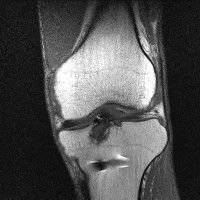

무릎 mri 간단히 봐주실 수 있으시나요 ㅠㅠ

안녕하세요 8년전 십자인대 수술하고 최근 무리한 운동에 무릎 불편감이 생겨서

mri 찍었습니다.

진단결과는 첫 찍은 병원에서 활액막염 이라는 진단을 받았습니다. 혹시 봐주실 수 있으실까요?

올라온 MRI가 단편적이라서 정확한 진단에 어려움이 있지만 십자인대에는 큰 이상이 있지는 않은것 같으며, 무릎관절내 물이 있는 것으로 보아 활액막염의 진단이 맞을 것 같습니다.

하지만 단편적인 영상이기 때문에 촬영병원에서 정확한 판독지 등을 받으시는 것이 좋겠습니다.